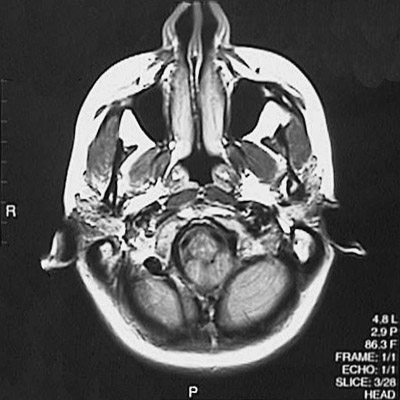

This is a normal axial proton density MRI scan demonstrating the nasal septum and concha and maxillary sinus and medulla and cerebellar hemisphere and cerebellar tonsil.